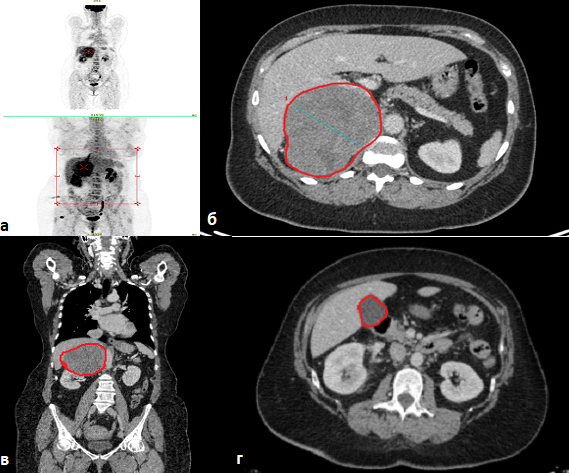

В августе 2022 г. зафиксировано второе прогрессирование – помимо увеличения уже имеющихся очагов появились новые в обоих легких и левой доле печени.

В сентябре 2022 г. пациентка направлена в отделение химиотерапии (ХТ) ГБУЗ «МКНЦ им. А.С. Логинова», где проведено 6 курсов противоопухолевого лечения в режиме EDP (доксорубицин 40 мг/м2 внутривенно в 1-й день, этопозид 100 мг/м2 внутривенно во 2–4-й дни, цисплатин 40 мг/м2 внутривенно в 3 и 4-й дни, цикл каждые 28 дней) на фоне продолжающейся терапии митотаном и октреотидом.

После проведенного лечения по клинико-лабораторным данным и результатам ПЭТ-КТ с 18-фтордезоксиглюкозой отмечается стабилизация заболевания, которая сохраняется уже на протяжении 16 мес (по состоянию на март 2024 г.).